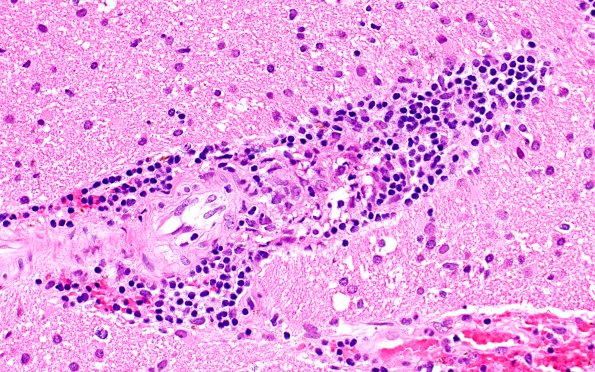

Washington University Experience | VASCULAR | Vasculitis - PACNS | 17B4 Vasculitis (Case 17) H&E 40x 2

Numerous parenchymal vessels, both arteriolar and venous, showed a lymphohistiocytic infiltrate and various degrees of occlusion. Vessels had only minimal angionecrosis and equivocal fibrin deposition. (H&E)